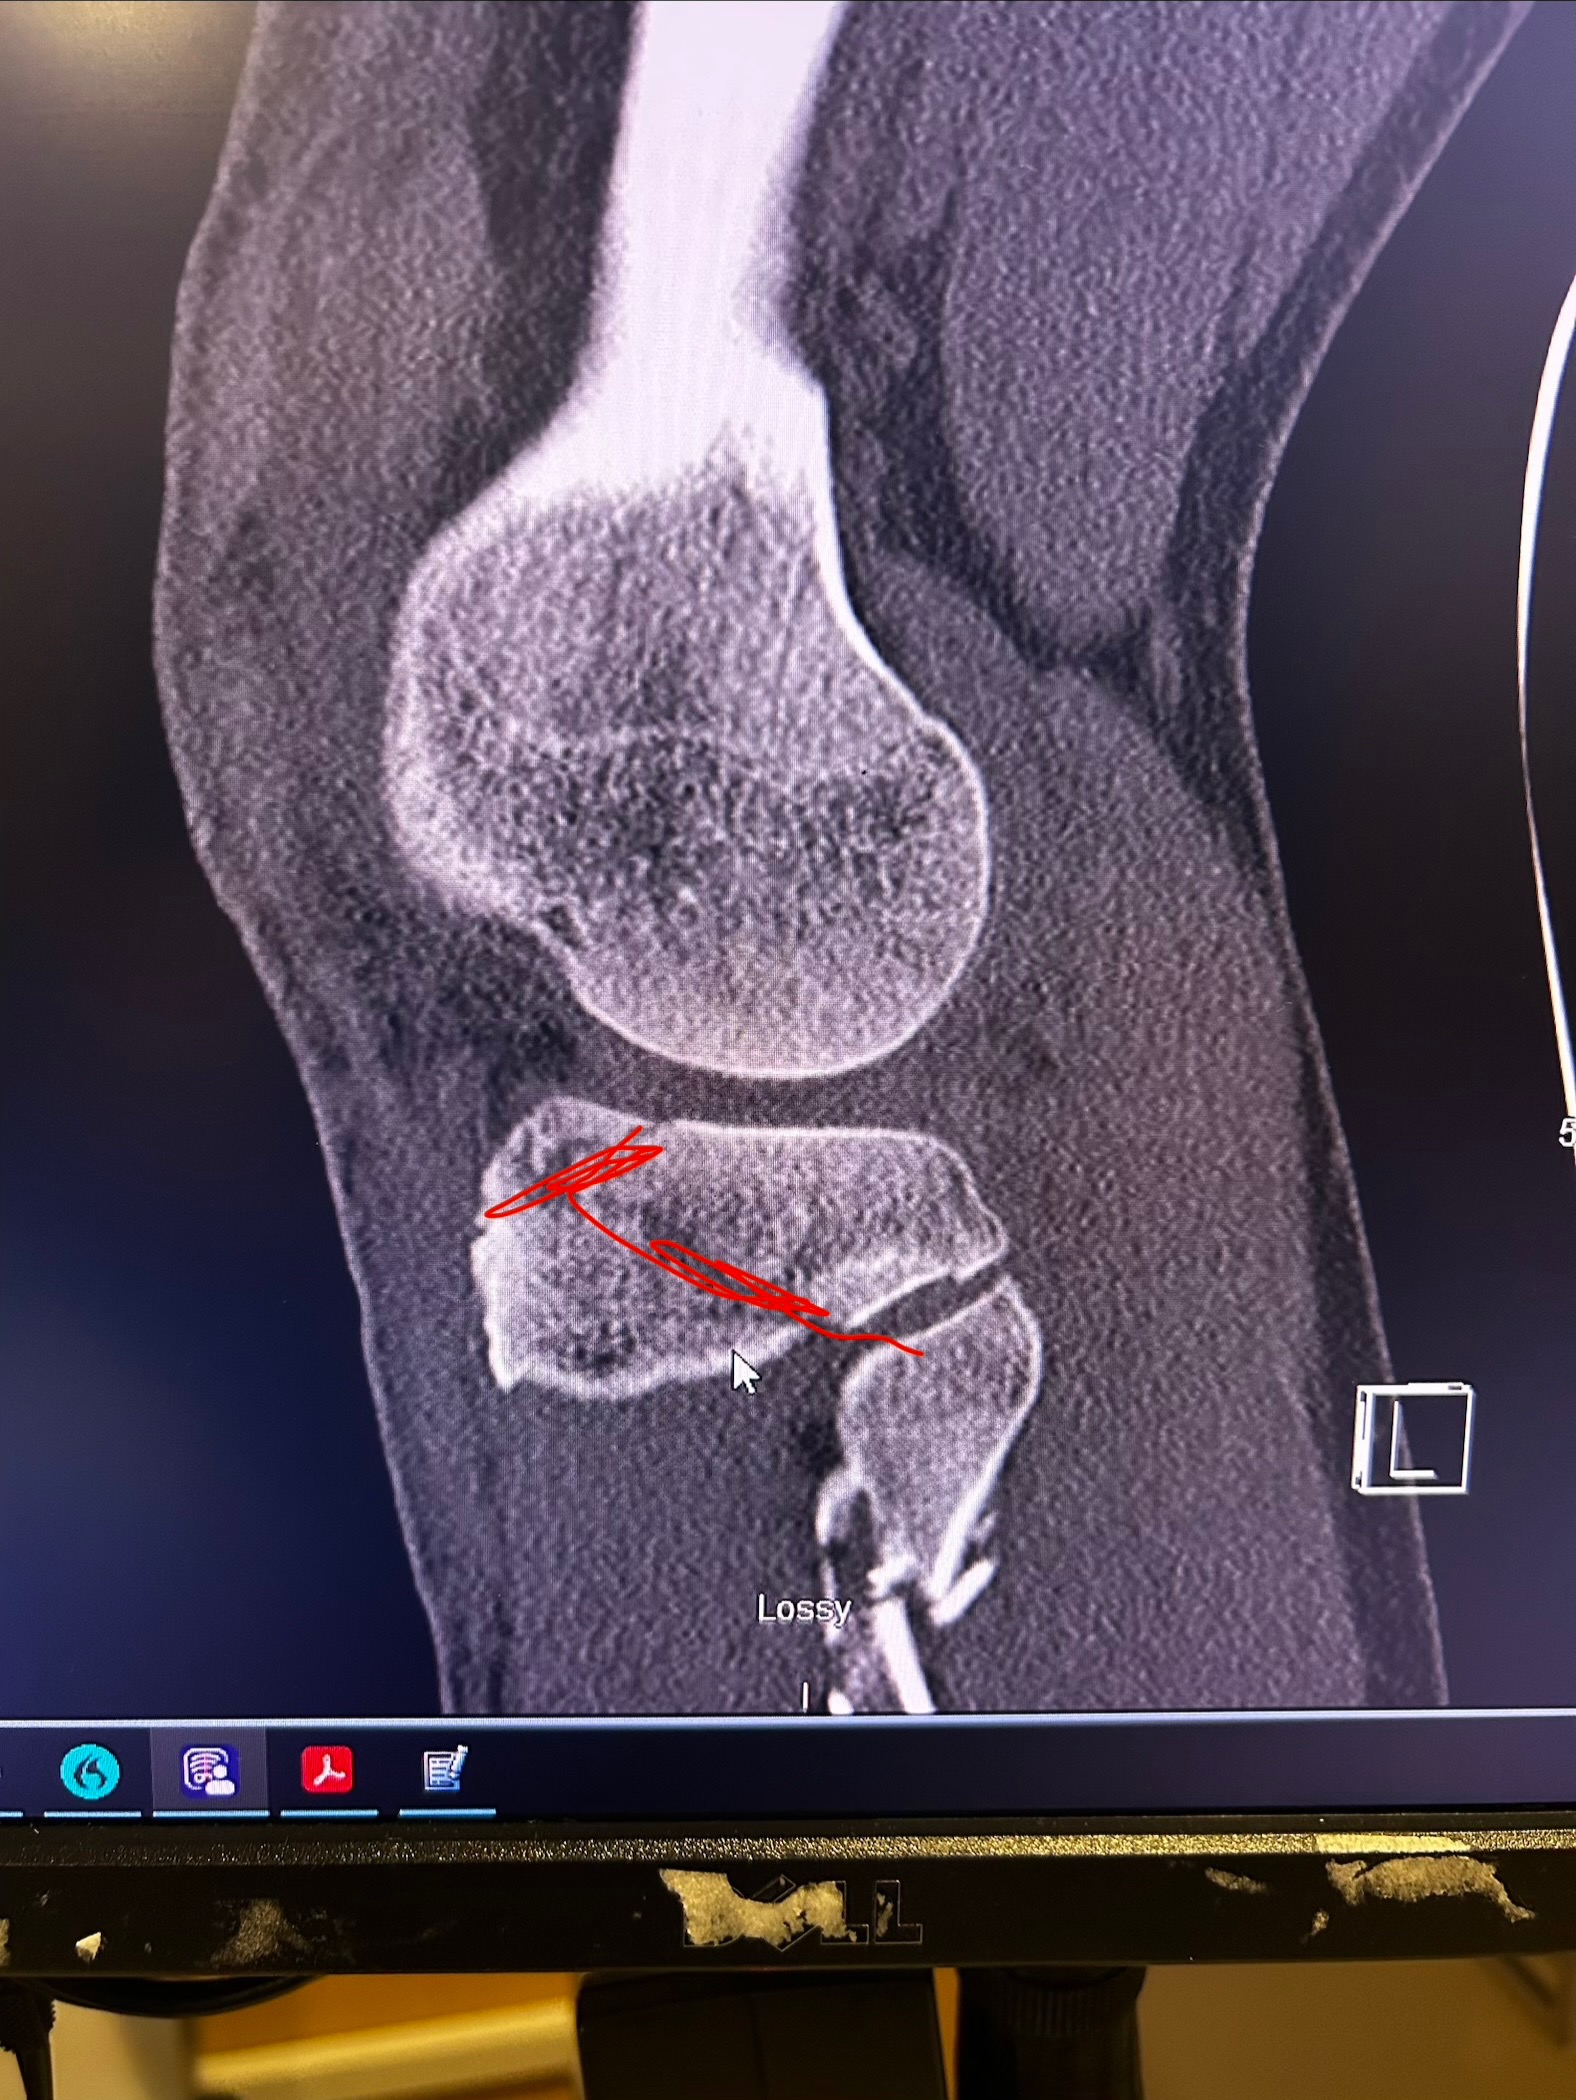

On January 22nd at 10:49 AM, I got the call no one ever wants to receive. It was John, screaming that he had fallen. In that moment, everything stopped. John fell approximately 20–25 feet, causing severe injuries from his left knee down. We are incredibly grateful and beyond blessed that he is alive today, because this situation could have ended very differently.